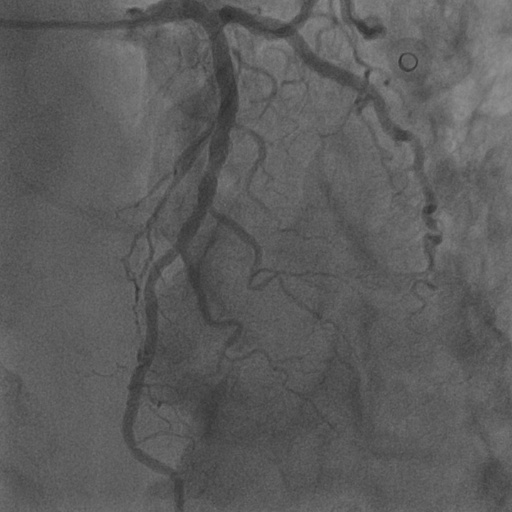

4.1 XACV Dataset

We collect 111 complete records of coronary artery X-ray videos, encompassing the injection, flow through the blood vessels around the heart, and dissipation of the contrast agent. Subsequently, we establish the XACV (X-ray Angiography Coronary Video) dataset. Each video consists of varying numbers of high-resolution coronary artery X-ray images. We invite experienced radiologists to annotate the vascular regions, focusing on one or two frames where the contrast agent is most prominent in each video. The XCAD dataset contains only a single image, and the CADICA video dataset does not provide corresponding ground truth. Therefore, in the following experiments, we conduct all the analyses on our collected XACV dataset and the corresponding GT for each sequence. In Figure 5, we show that compared to other publicly available datasets, XCAD [33] and CADICA [19], our dataset exhibits finer annotations in the vascular regions, providing an advantage for future related tasks. The development and use of our dataset have been approved by our institution’s IRB.